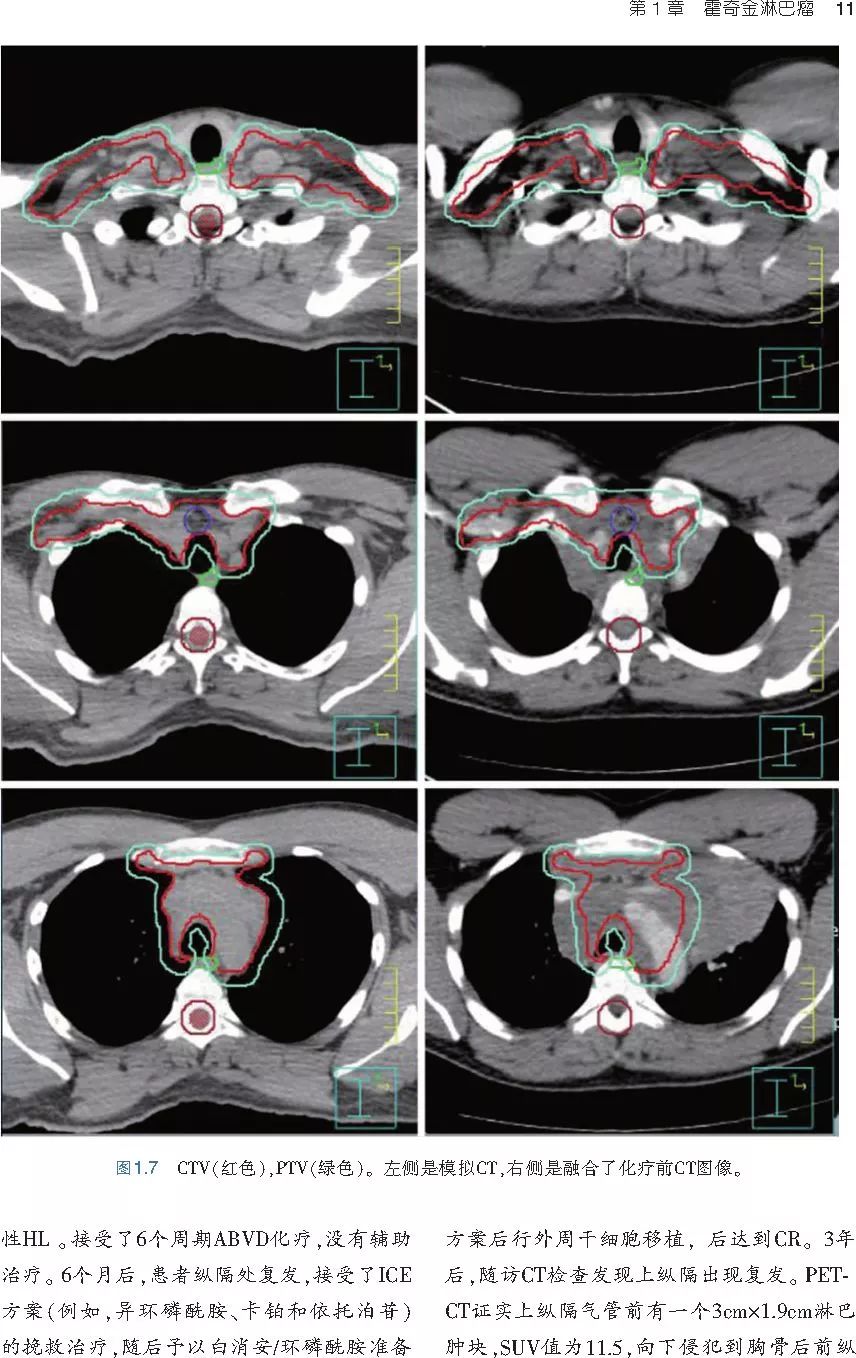

❤ 展开疾病诊断、病理描述及治疗方向的详细阐述,包含医学影像,图文并茂,深入浅出。

本书案例讨论遵循标准格式,包括临床描述,其次是与诊断相关的病理描述和分期,然后详细讨论治疗选择。最后,确定治疗方案,并提供所使用的规划放疗技术/方式的图像。对放射肿瘤医生进行临床决策非常有帮助,对于血液病临床医生也有很好的指导作用。